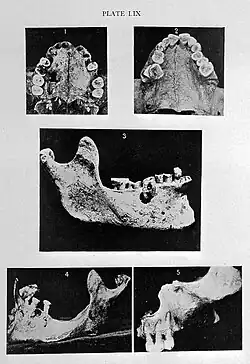

3 Periapikales Granulom

Makedonische Zeit:

2 Abrasionsgebiss

Römische Zeit:

5 Osteolyse

Koptische Zeit:

1 Gaumenperforation, 4 Zyste

Nur wenige Untersuchungen wurden bislang in der Neuzeit an mittelalterlichen Leichnamen vorgenommen, um etwa die Parodontitis-Erreger zu bestimmen. Im Rahmen einer Studie konnten größere Mengen Erbsubstanz aus dem Zahnstein eines 1000 Jahre alten Skeletts isoliert und entschlüsselt werden. Es handelt sich dabei um Zahnstein eines Mannes, der im Kloster Dalheim (Lichtenau) lebte. Dabei konnten wesentliche Teile des Genoms eines Parodontitis-Bakteriums rekonstruiert werden, und es wurde erstmals Erbmaterial von Nahrungsbestandteilen gefunden, darunter 40 opportunistische Erreger, Antibiotika-Resistenzgene, es gelang die Genomrekonstruktion des parodontalen Krankheitserregers Tannerella forsythia, von 239 Bakterien- und 43 menschlichen Proteinen. Die Entdeckung weist den Weg zu einem besseren Verständnis von Zahn- und Zahnfleischerkrankungen und zeigt auf, wie sich die menschliche Mundflora sowie Volkskrankheiten in der menschlichen Evolution entwickelt und angepasst haben.[122]